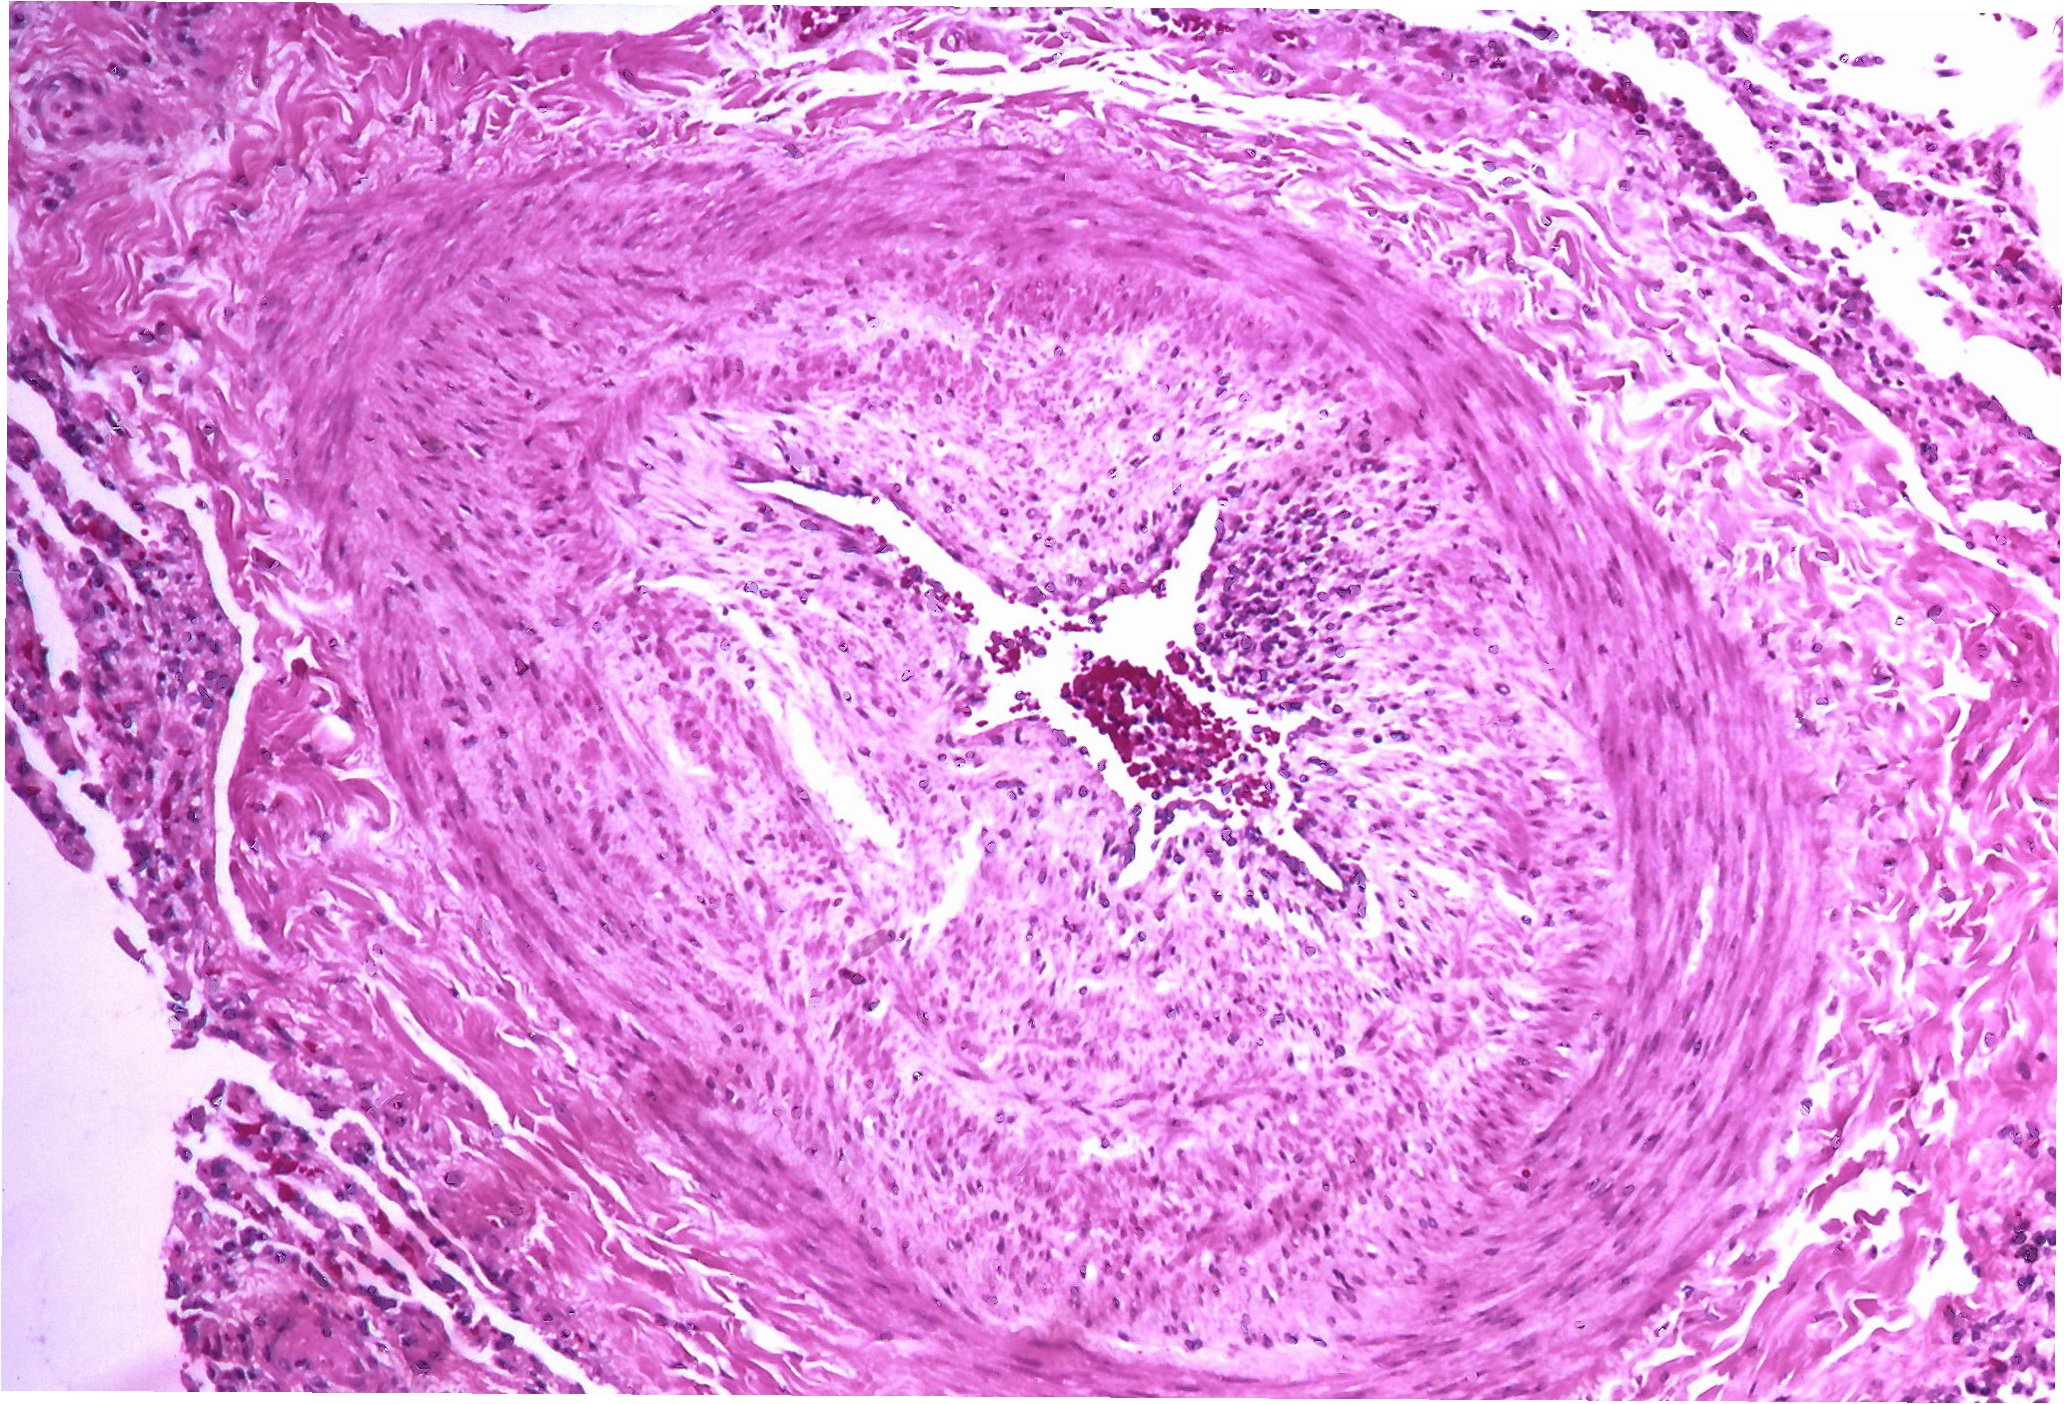

폐동맥 고혈압은 폐동맥의 평균 압력이 휴식 시 25mmHg 이상, 운동 시 30mmHg 이상으로 상승하는 상태를 의미합니다. 이는 폐동맥 혈관이 좁아지거나 막혀 혈액 흐름에 저항이 증가하면서 발생합니다. 폐동맥 고혈압은 다양한 원인에 의해 발생할 수 있으며, 특정한 원인 없이 발생하는 경우도 있습니다. 이러한 경우를 특발성 폐동맥 고혈압이라고 합니다. 폐동맥 고혈압은 폐의 혈관에 영향을 미쳐 심장으로 가는 혈액의 흐름을 방해합니다. 이로 인해 심장은 혈액을 폐로 밀어내기 위해 더 열심히 일해야 하며, 결국 심장에 부담이 가중되어 심부전으로 진행될 수 있습니다.

폐동맥 고혈압은 다양한 검사를 통해 진단합니다. 먼저, 병력 청취 및 신체 검사를 통해 환자의 증상과 전반적인 건강 상태를 파악합니다. 이어서 다음과 같은 검사들을 시행합니다. 첫째, 심전도 검사입니다. 심장의 전기적 활동을 측정하여 심장의 이상 여부를 확인합니다. 둘째, 흉부 X-ray 검사입니다. 폐와 심장의 상태를 확인하고, 폐동맥 확장을 관찰합니다. 셋째, 심장 초음파 검사입니다. 심장의 구조와 기능을 평가하고, 폐동맥 압력을 추정합니다. 넷째, 폐 기능 검사입니다. 폐활량, 폐 확산 능력 등을 측정하여 폐의 기능 상태를 평가합니다. 다섯째, 혈액 검사입니다. 혈액 가스 분석, 심장 효소 검사 등을 통해 폐와 심장의 상태를 확인합니다. 여섯째, 우심 도자술입니다. 폐동맥 압력을 직접 측정하고, 폐동맥 고혈압의 심각도를 평가하는 가장 정확한 검사 방법입니다. 이러한 검사들을 종합하여 폐동맥 고혈압을 진단하고, 질병의 심각도를 평가합니다.